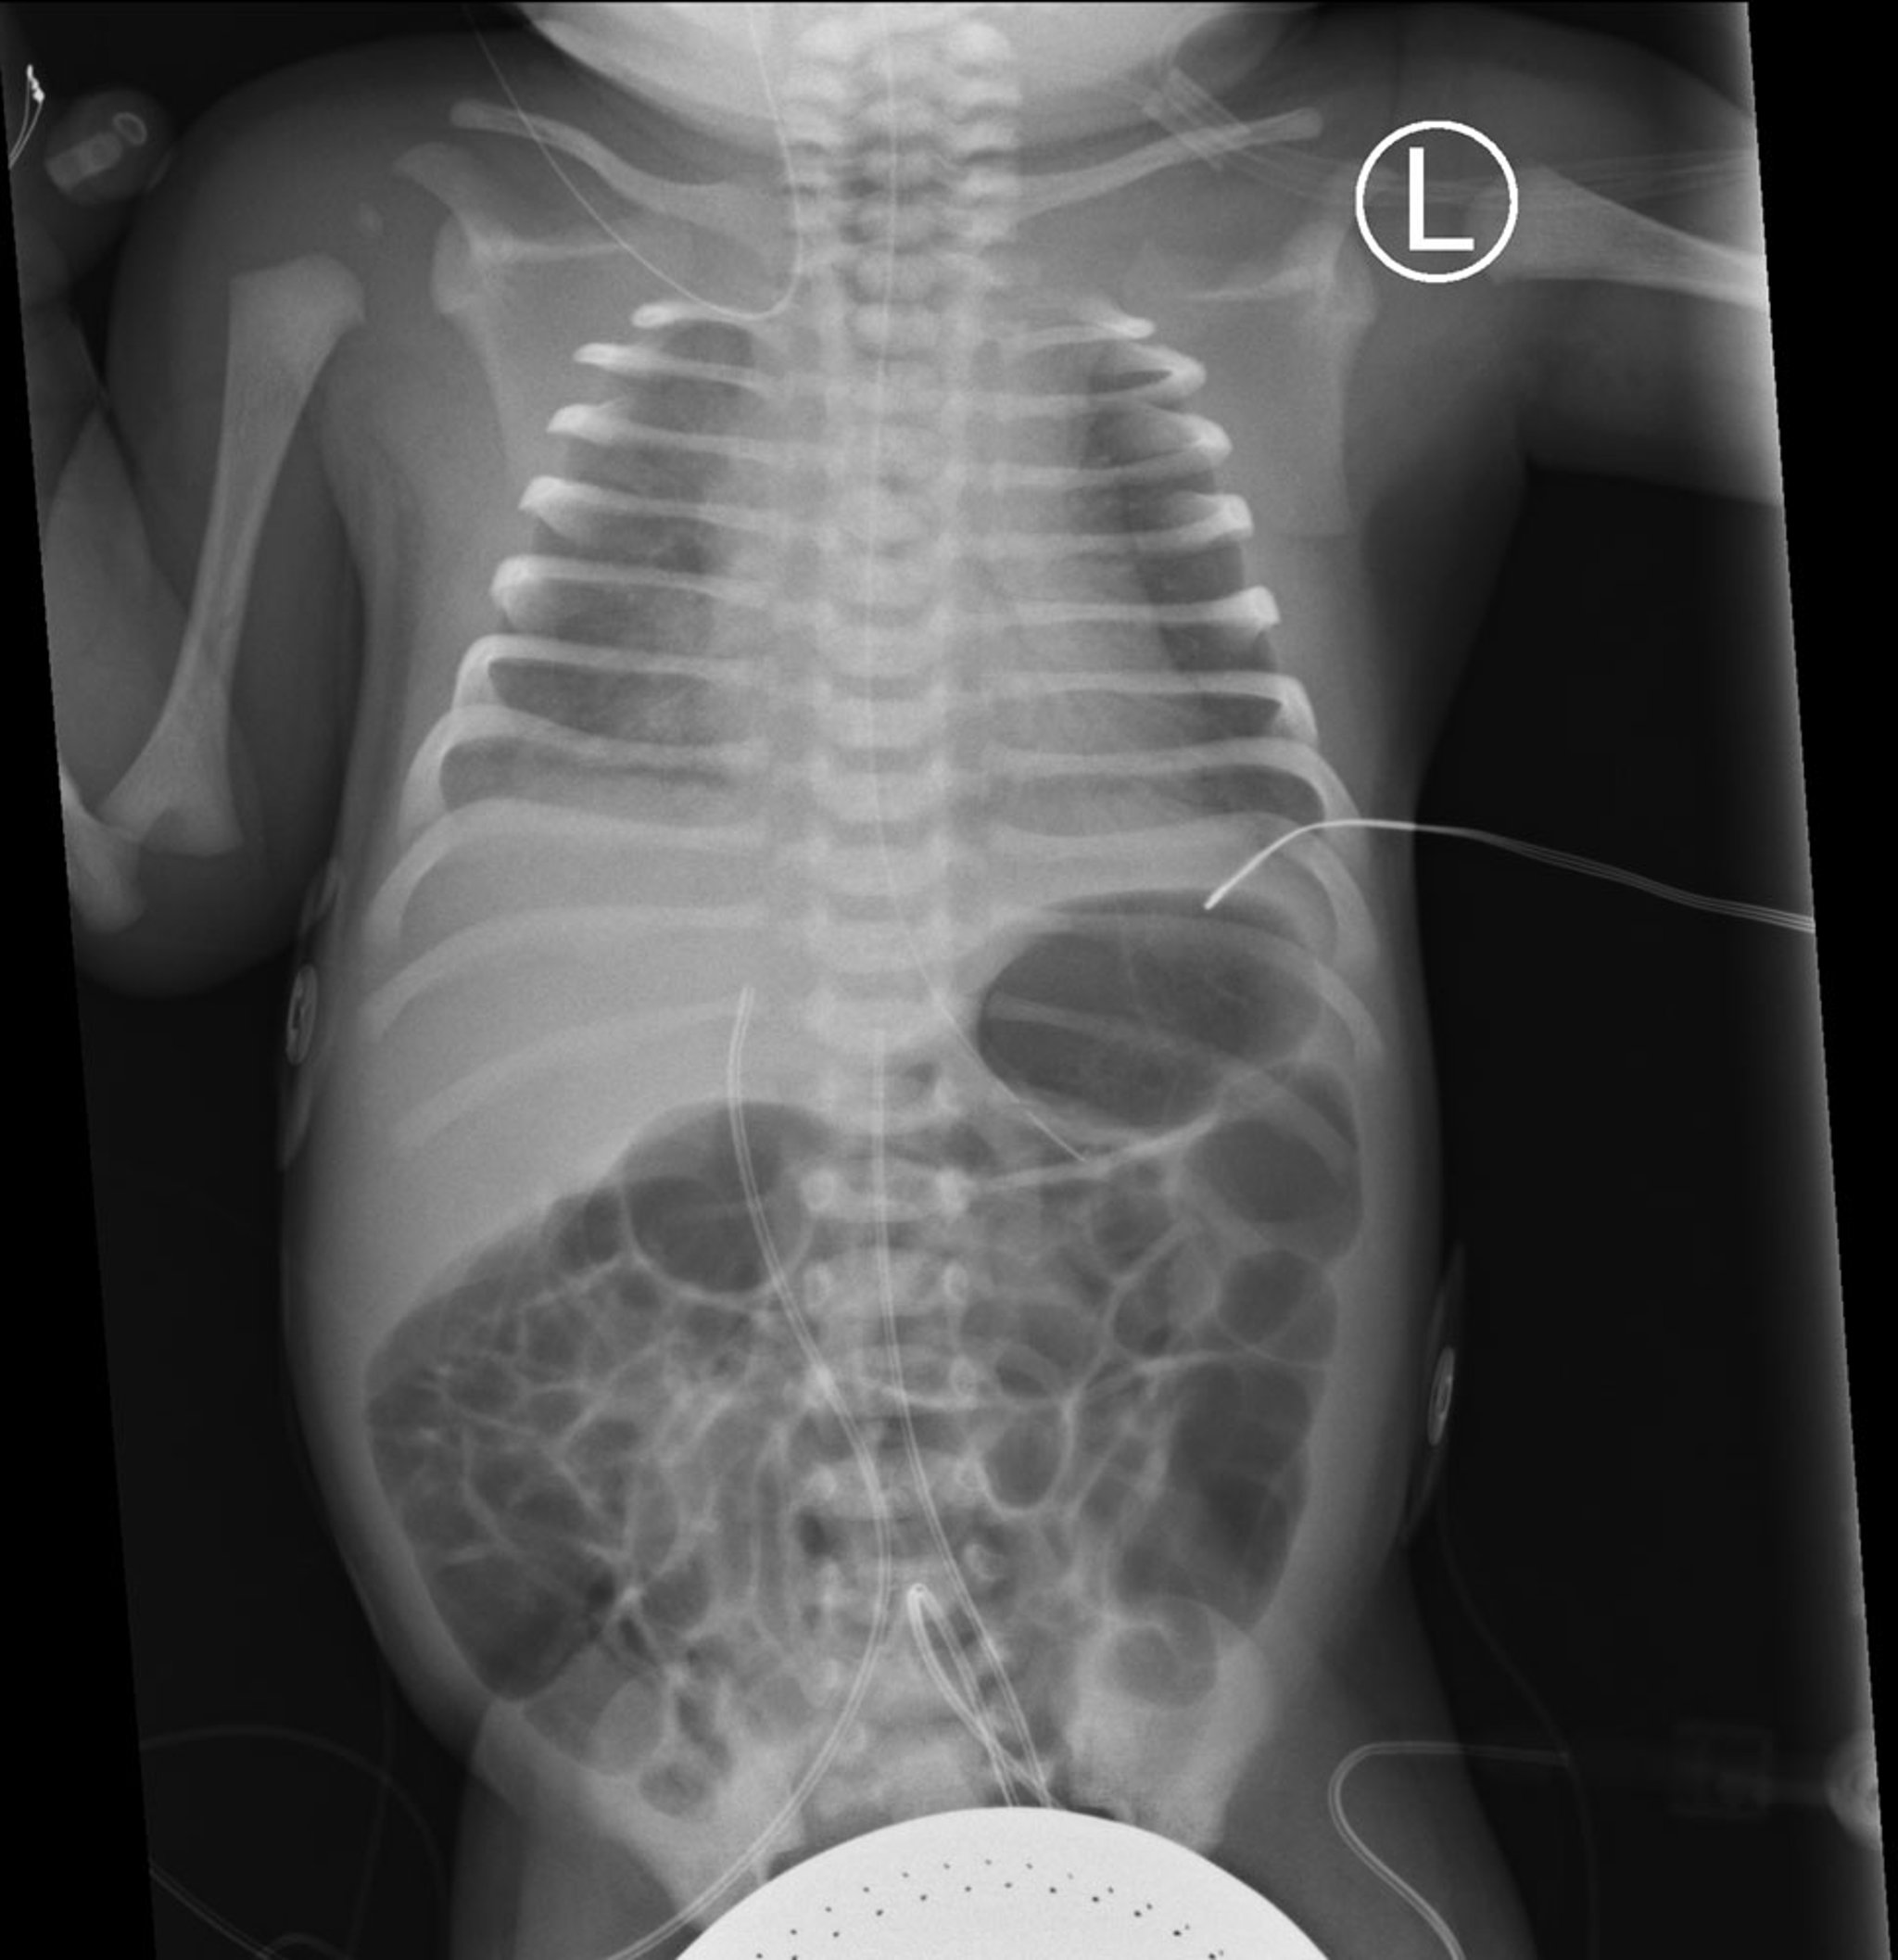

This frontal view of a chest and abdominal radiograph shows bilateral diffuse ground-glass opacity in both lungs with air bronchograms, consistent with respiratory distress syndrome (RDS).

Also seen are an orogastric tube as well as umbilical artery and venous catheters in expected positions.